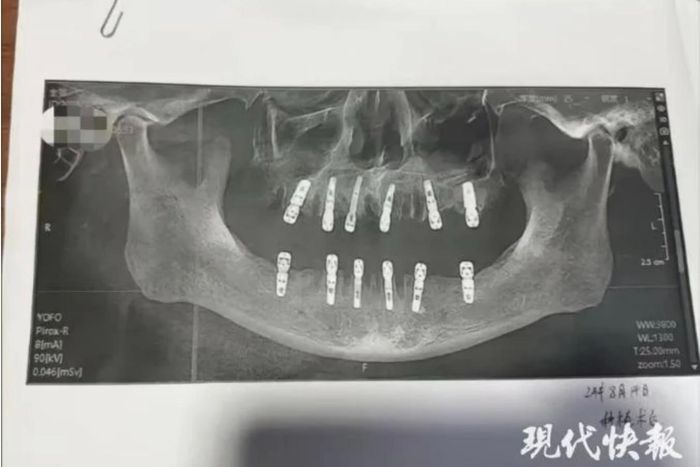

TRUNG QUỐC - Nhà chức trách đang điều tra vụ việc một người đàn ông lớn tuổi tử vong 13 ngày sau khi nhổ 23 chiếc răng và trồng 12 cái trong cùng một ngày tại một phòng khám nha khoa.

Theo đơn đồng ý của bệnh nhân, cha bà Shu thực tế đã nhổ 23 chiếc răng tự nhiên rồi sau đó được khoan 12 lỗ vào xương hàm để trồng răng mới. Tất cả đều làm trong 1 ngày, đồng nghĩa với việc ông phải chịu cơn đau không thể tưởng tượng nổi sau khi thuốc tê hết tác dụng.